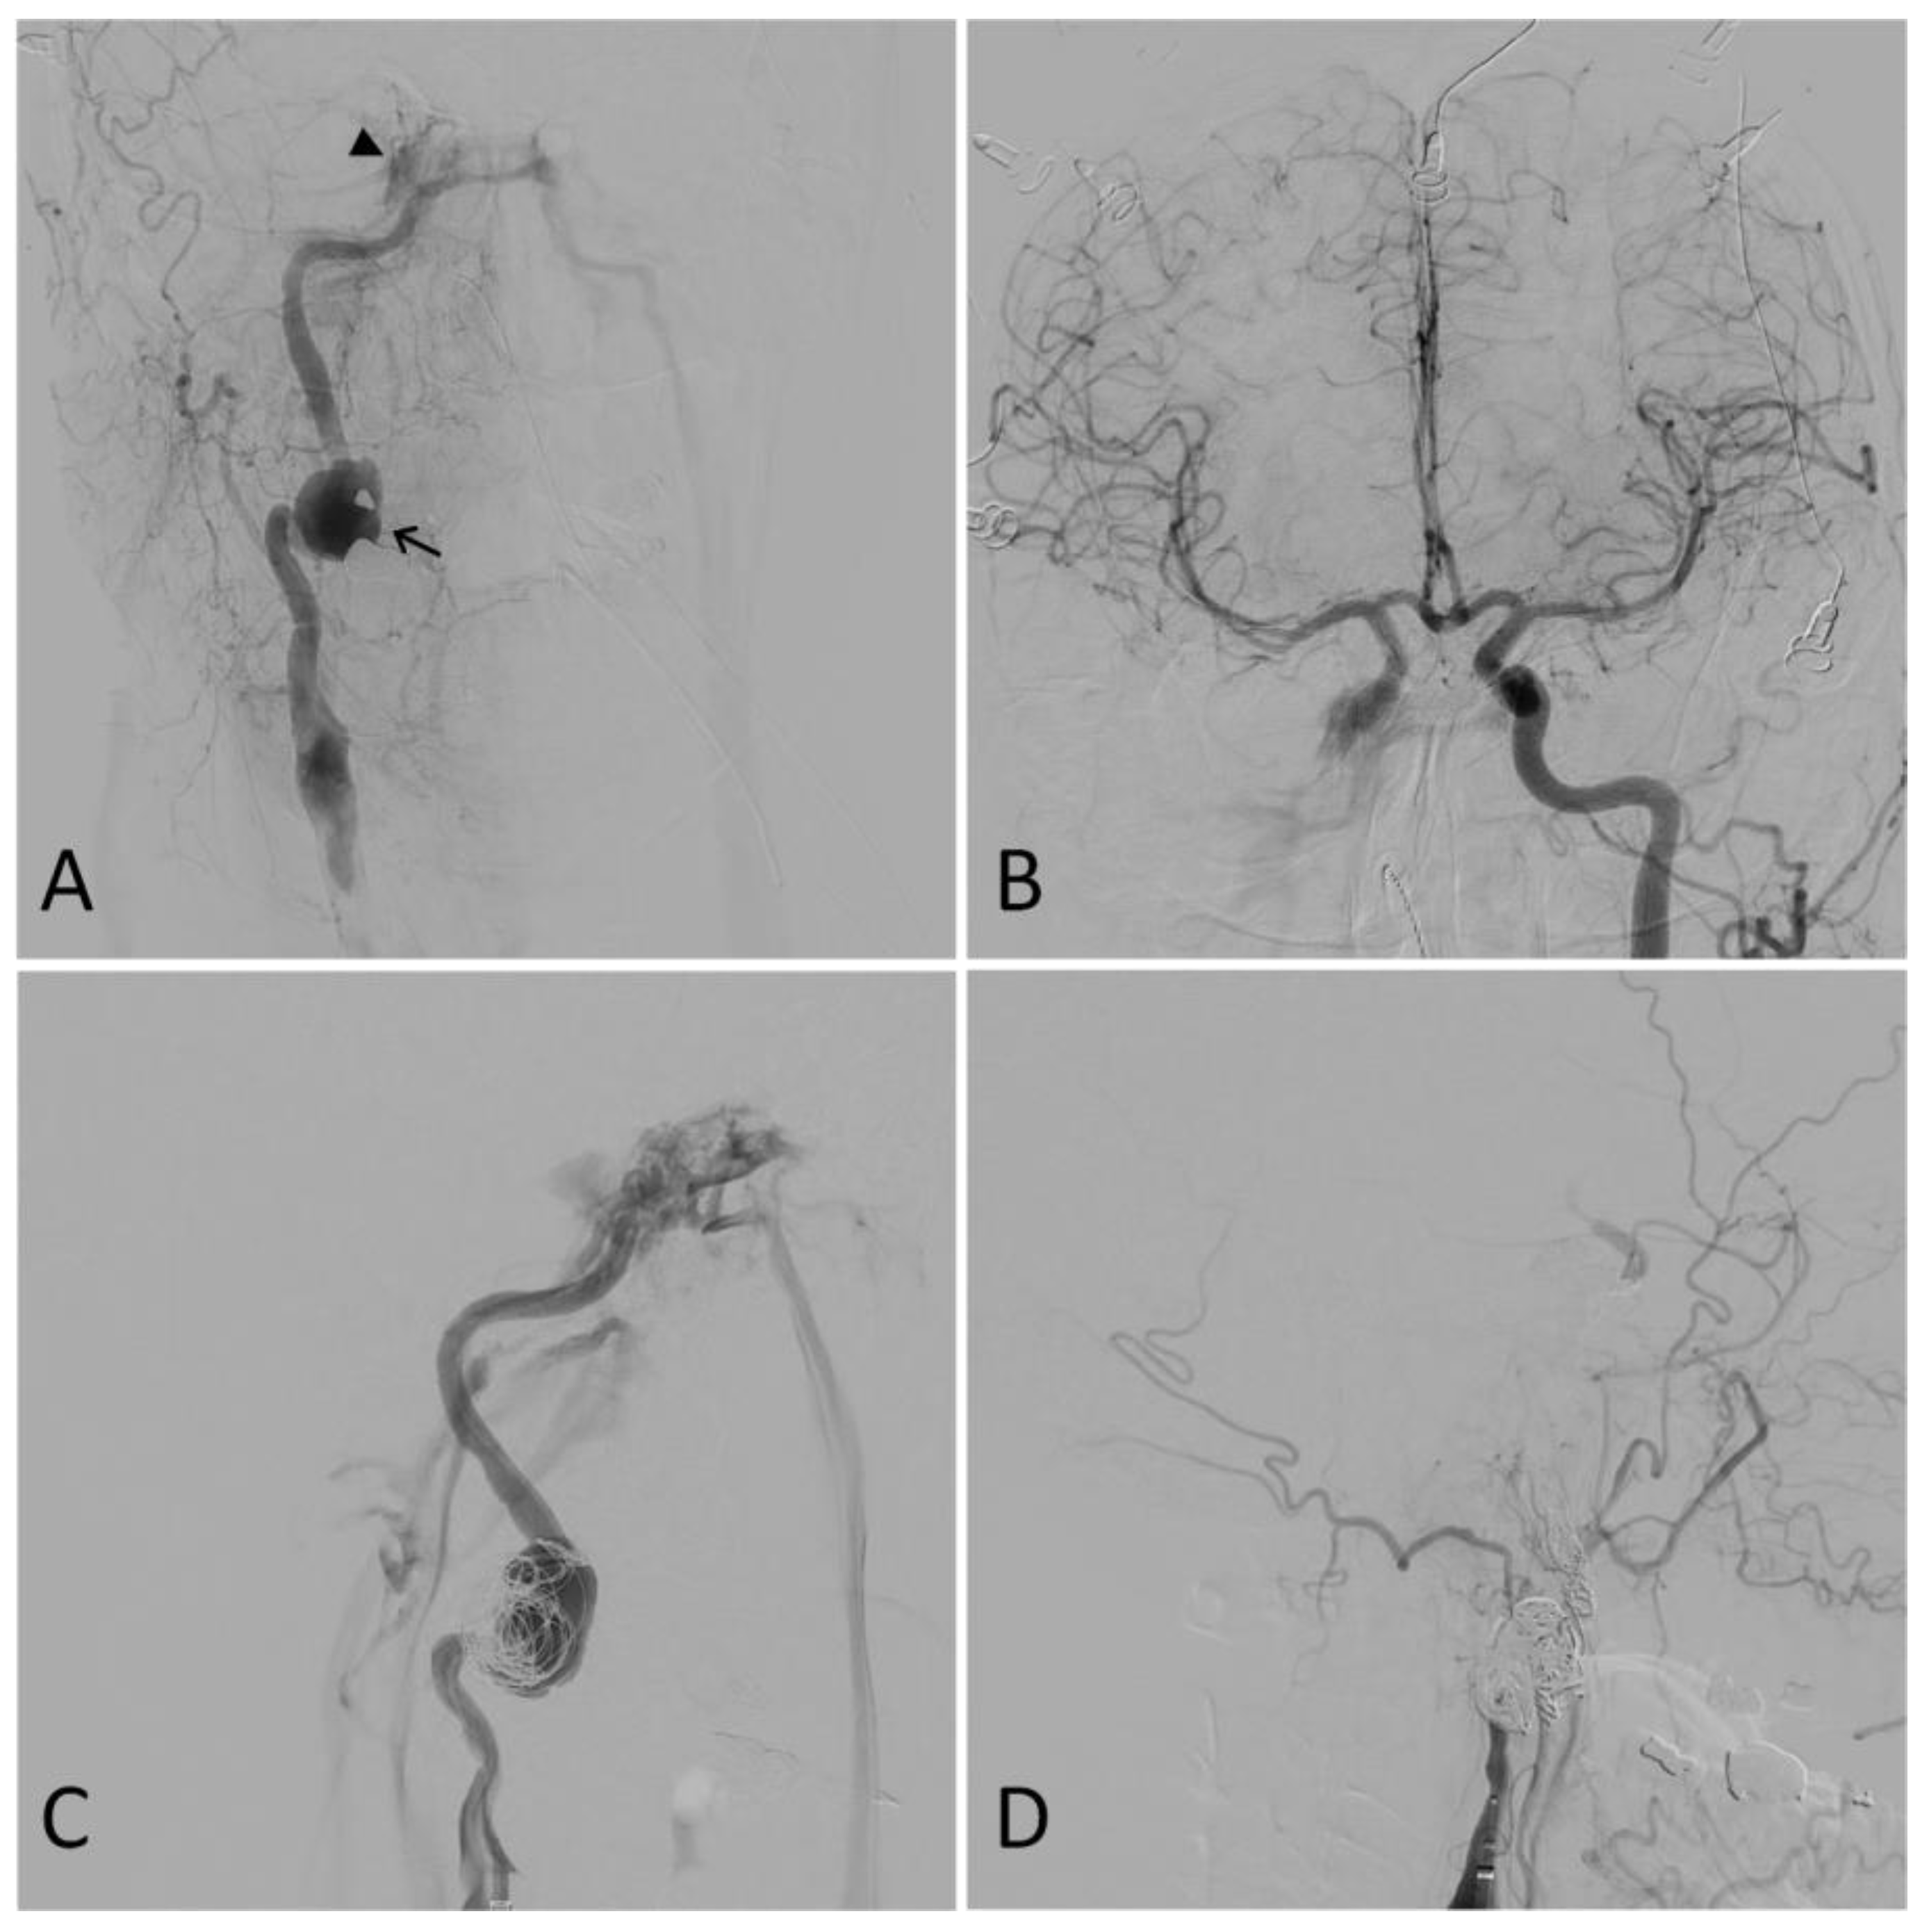

3.2. Grade III: Pseudoaneurysm

3.3. Grade IV: Occlusion

3.4. Grade V: Transection